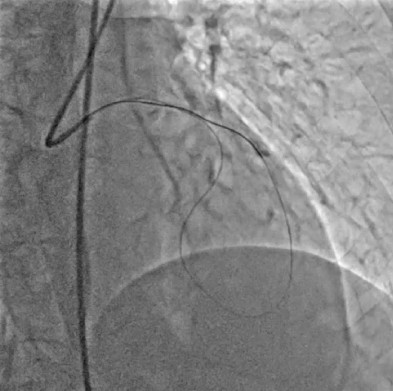

- Well-developed septal-to-septal collateral channels connecting the proximal septal branch of the LAD or LCX to distal LAD septal branches were identified and deemed suitable for retrograde approach.A Sion wire was advanced into the donor septal branch through the same guide catheter. Over the wire, a Corsair Pro XS microcatheter was carefully navigated through the septal collateral to reach the distal true lumen of the LAD, under fluoroscopic roadmap guidance

- Using a Gaia Second wire, the CTO segment was crossed retrogradely from the distal LAD into the proximal true lumen of the LAD.

- The microcatheter was advanced to provide support and facilitate wire manipulation.